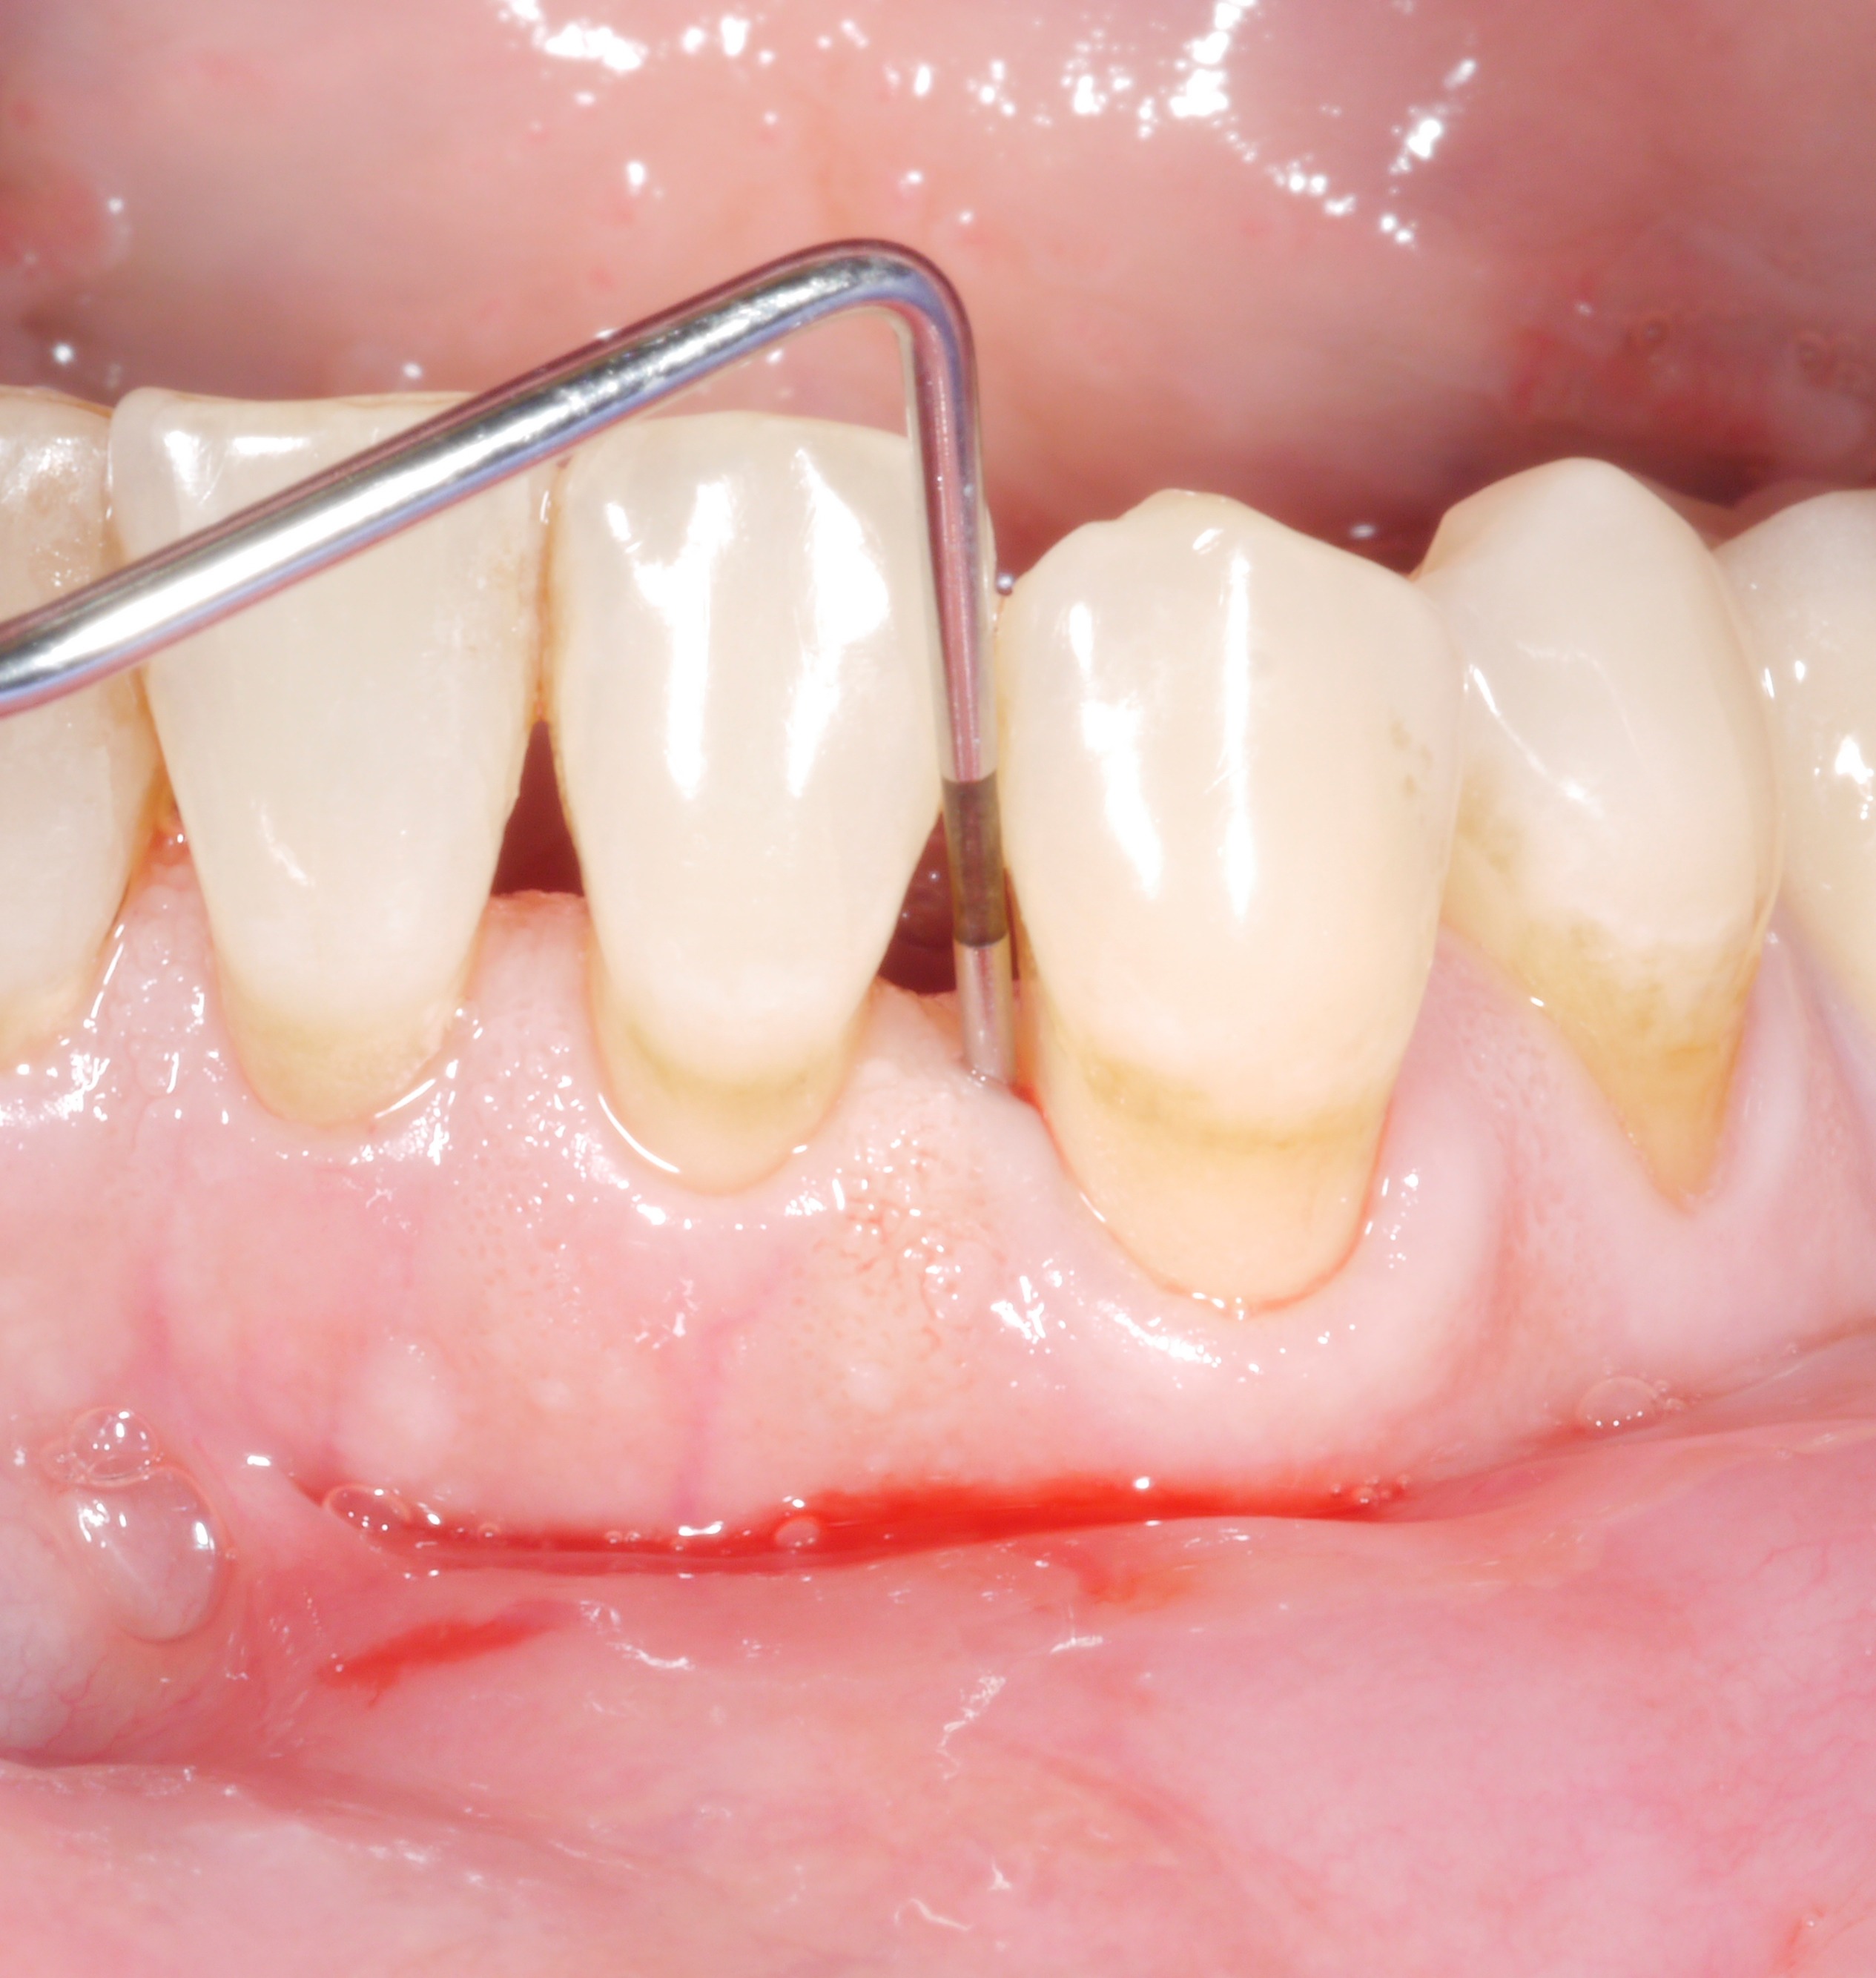

It is a situation we are all too familiar with: following the active phase of treatment, nearly all the patient’s teeth are now unaffected by increased pocket probing depths. However, there are still 1 or 2 places where the treatment goal has unfortunately not been achieved. The following thought might arise: “how bad can it be? A single pocket of 6 or 7 mm – surely that can’t make a big difference?

However, dentists should not rush to say they are content with residual pocket probing depths. This is because even individual residual pocket probing depths of more than 4 mm constitute a problem, as least in the longer term – both for the affected tooth and for the rest of the dentition.

• Bleeding on probing doubled the risk of later tooth loss.